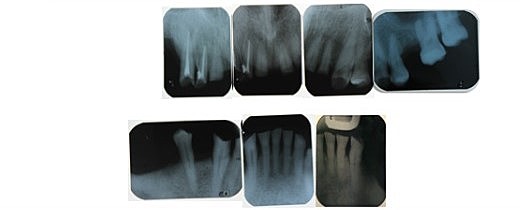

• Serie Radiográfica

Serie Radiográfica

Se tomó serie radiográfica para verificar cuanta pérdida ósea presenta. Se pudo observar que el paciente presentaba Pulpitis irreversible asintomática en los O.D: 1.1,2.1, 2.2,4.1.